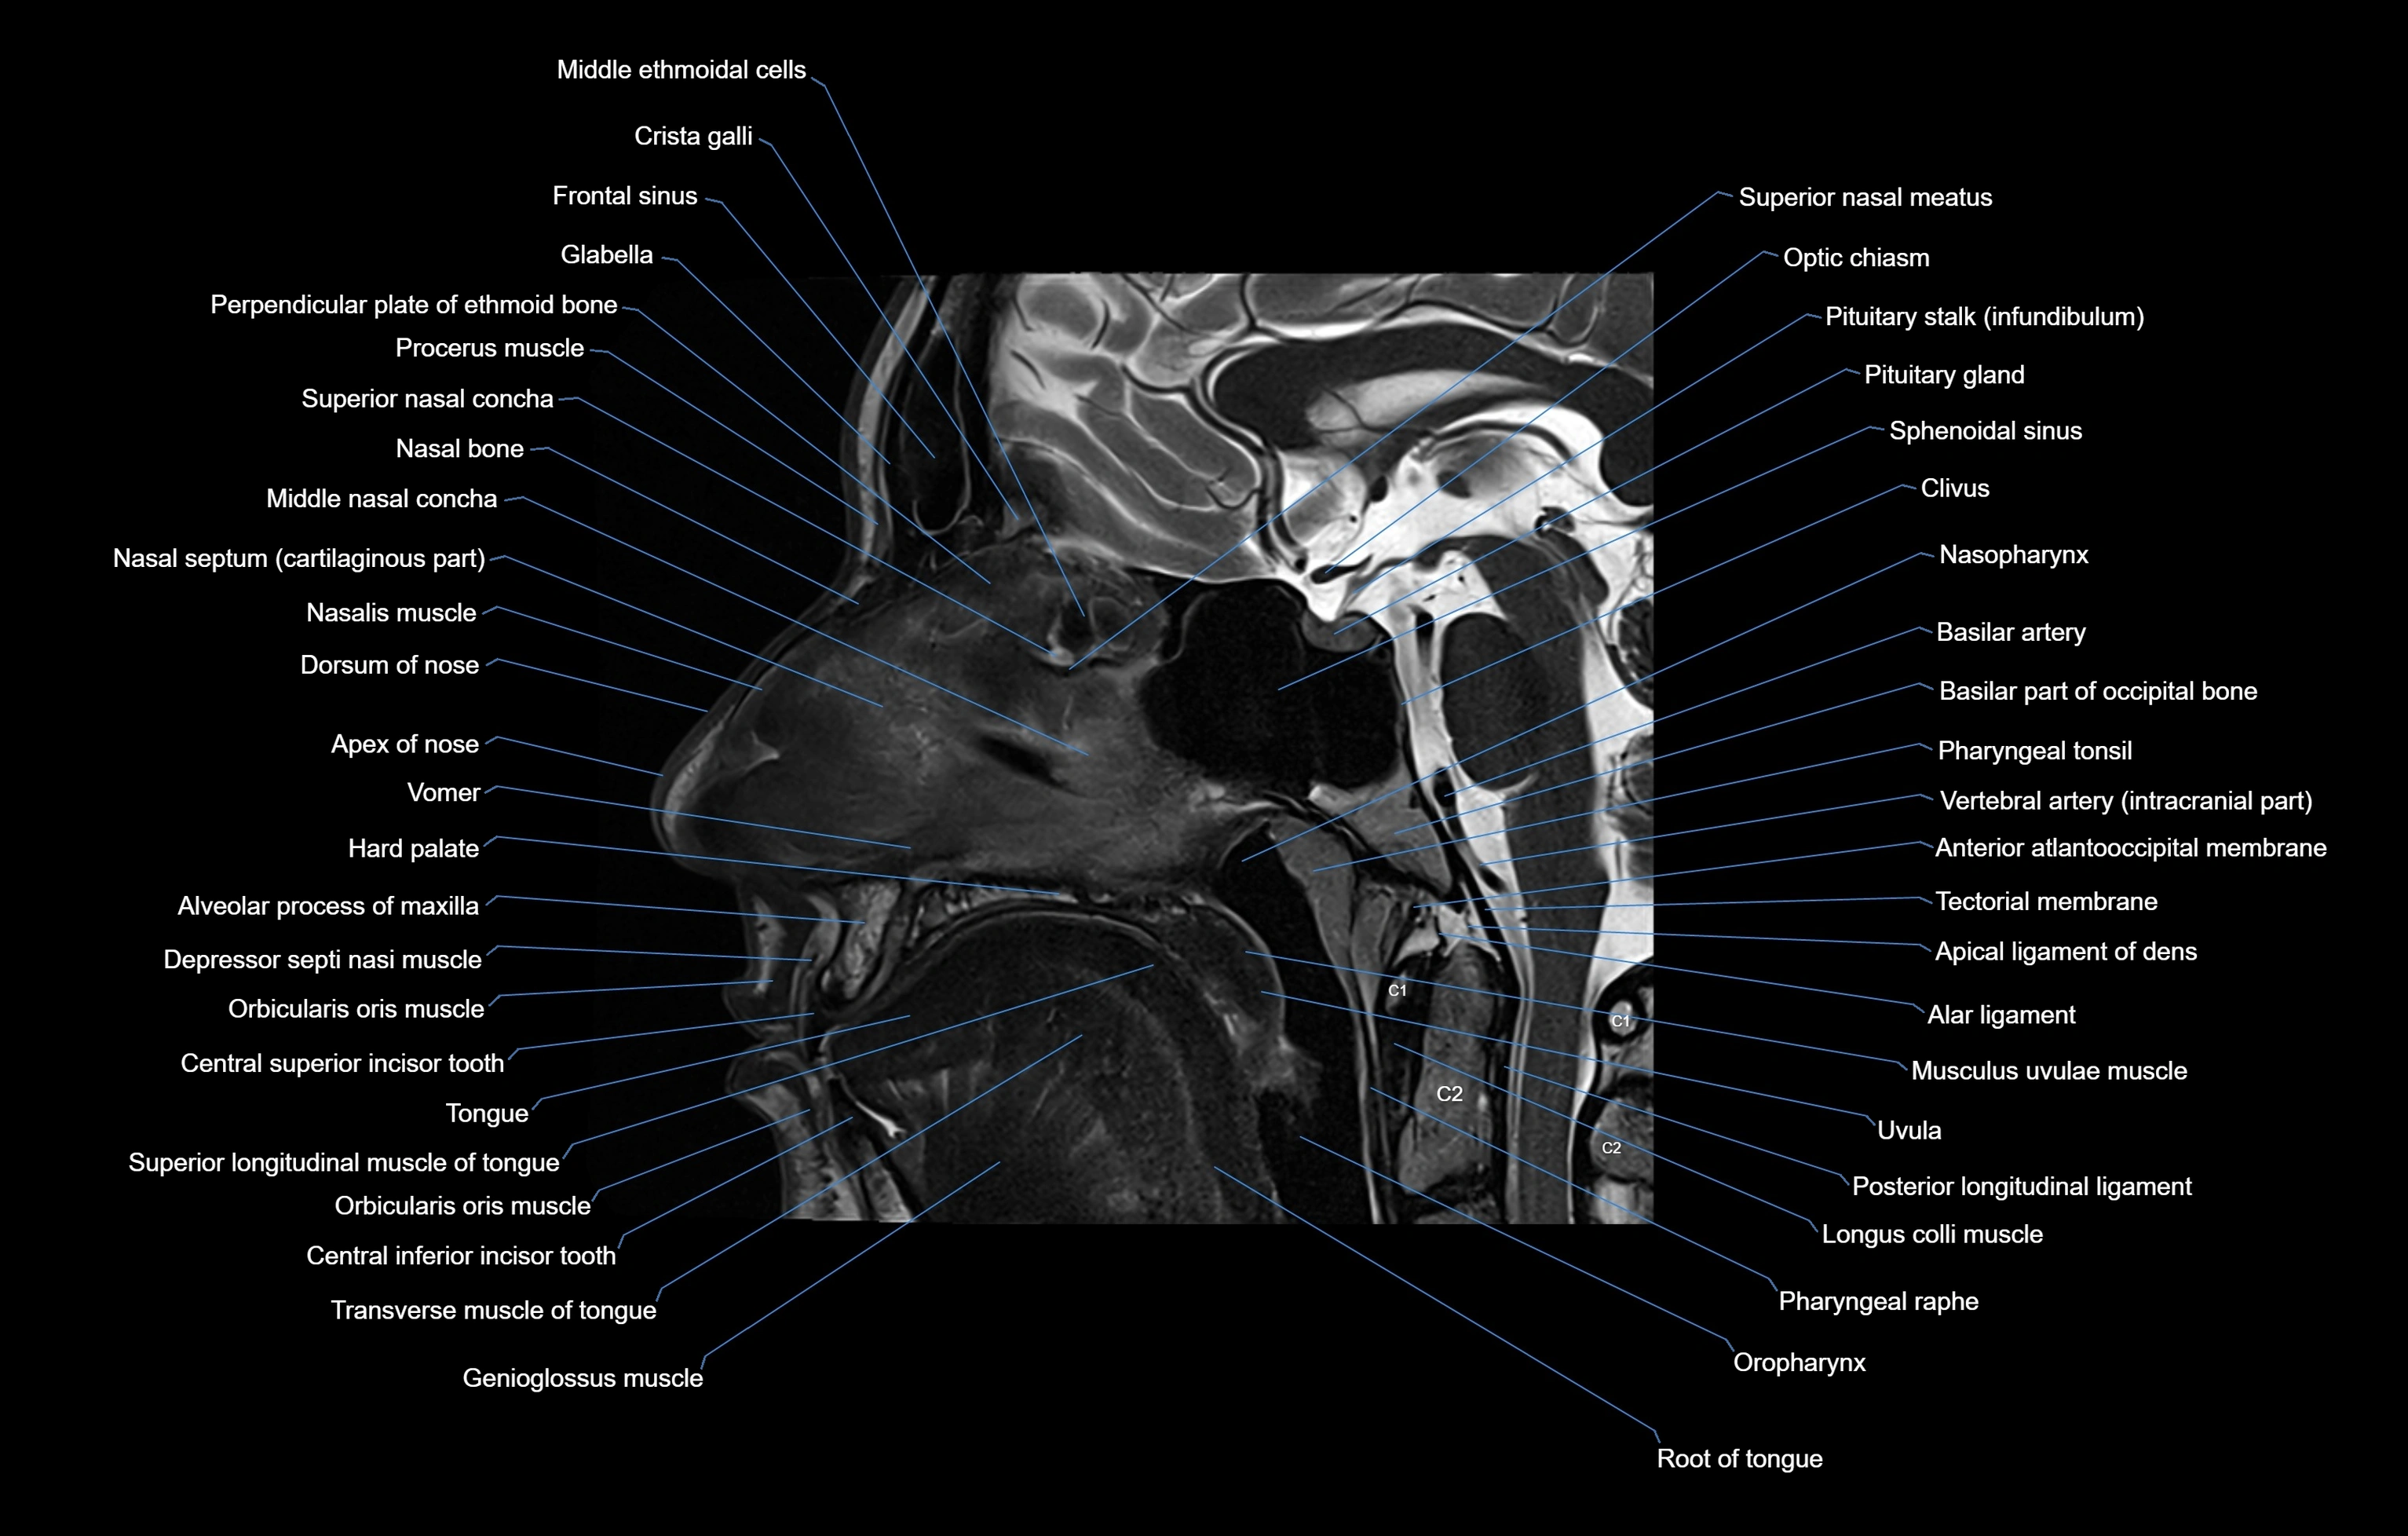

MRI images